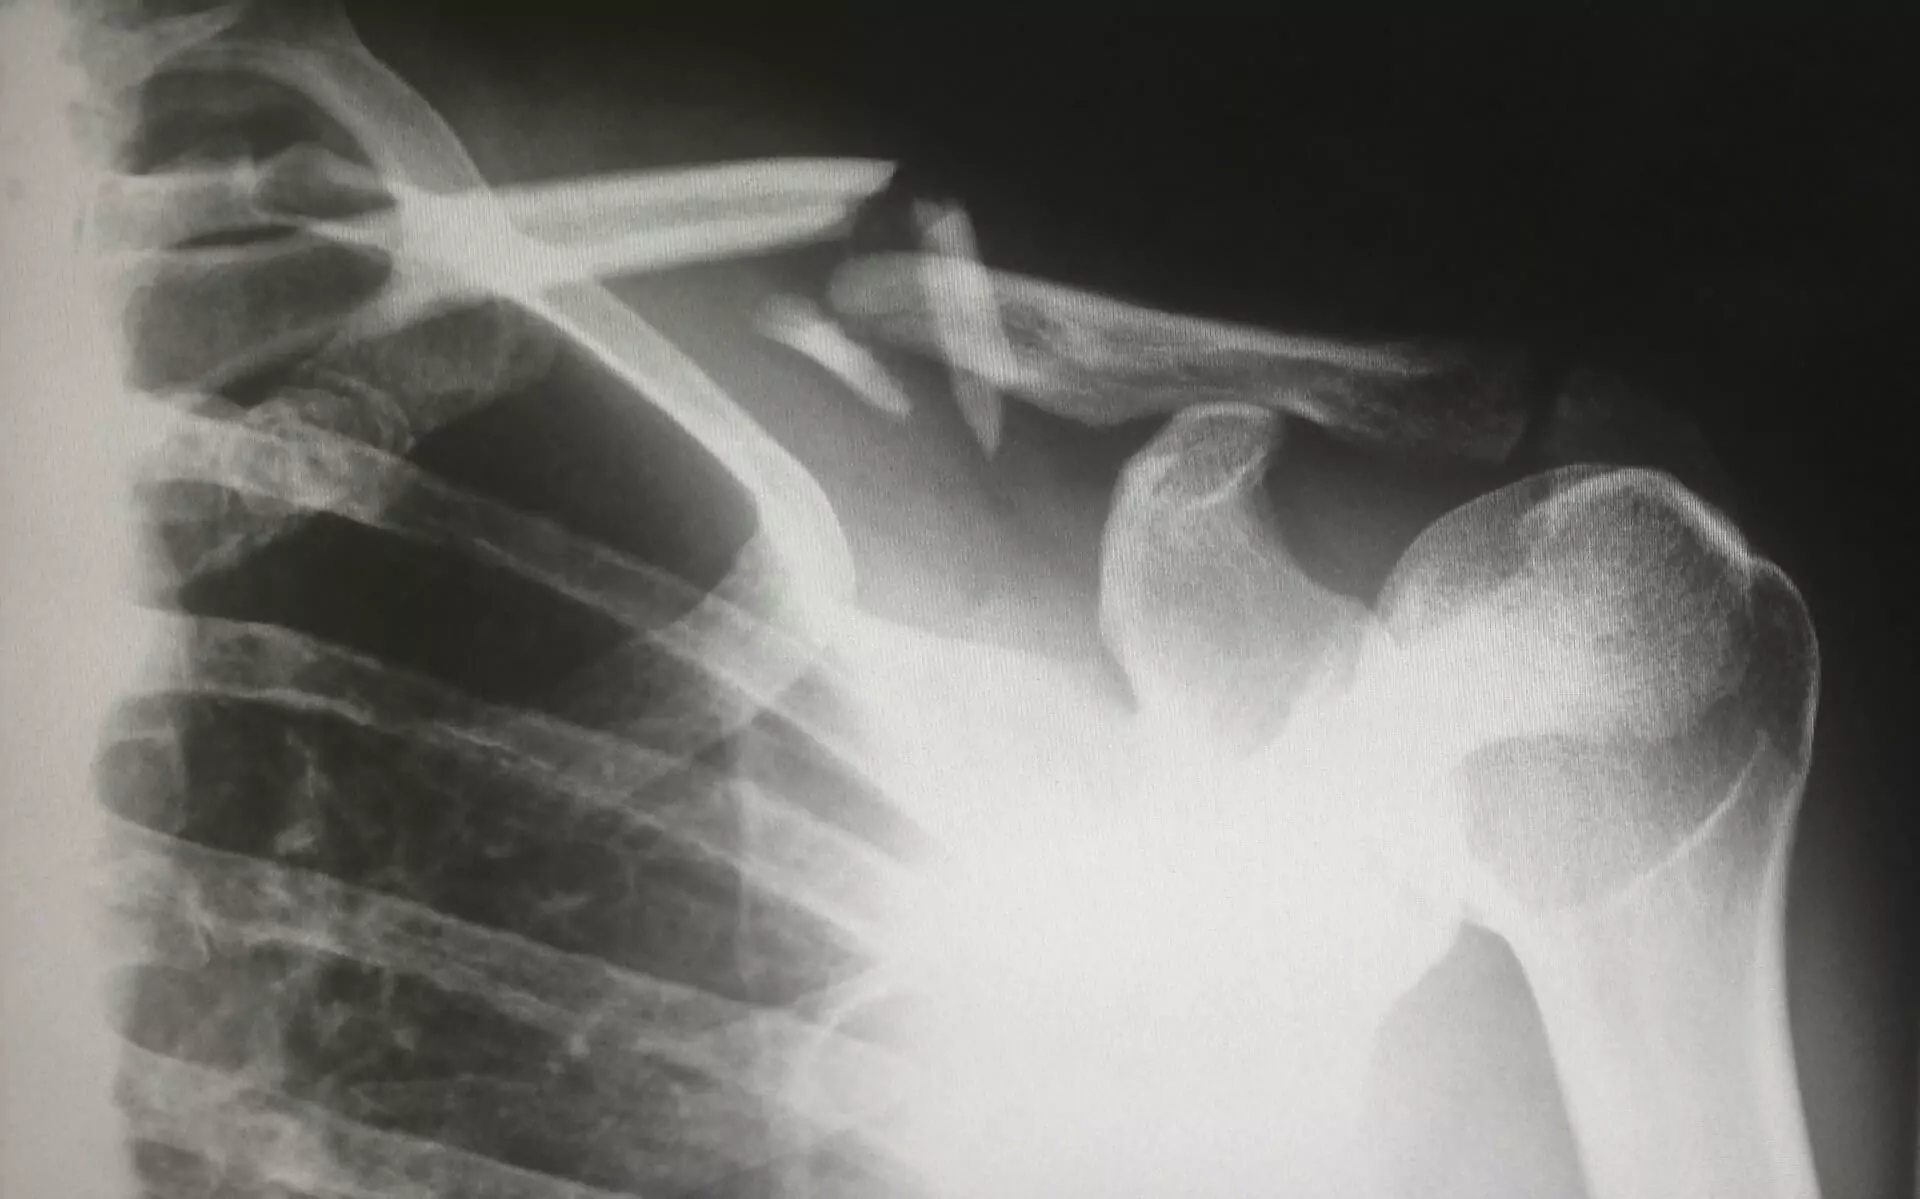

Identifying signs of abuse or neglect in a nursing home is critical to protecting the well-being of vulnerable residents. Broken bones, a common consequence of mistreatment, may not always be immediately apparent, especially when staff attempt to obscure the circumstances. However, there are clear indicators that families can watch for to recognize potential abuse.

Unexplained Fractures

Fractures without a credible explanation are a significant warning sign of nursing home abuse. When staff provide vague or inconsistent accounts of how an injury occurred, it raises serious concerns. For example, a resident with limited mobility is unlikely to have sustained a fall without assistance or intervention. In these situations, unexplained fractures warrant further investigation to determine whether abuse or neglect played a role.

Physical Signs of Trauma

Visible signs of trauma near the site of a fracture, such as bruises, redness, or swelling, often point to mishandling or abuse. In some cases, these injuries may show distinct patterns, like marks resembling handprints or objects, which can suggest intentional harm. Frequent or untreated physical injuries indicate a broader failure of care within the facility.